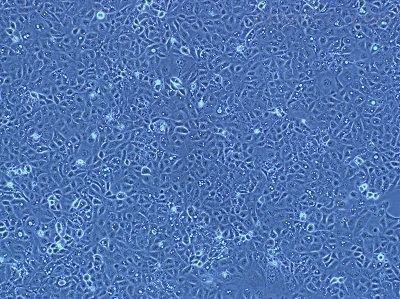

该细胞是从一名13岁的白人女性的骨肉瘤组织中分离建立的,表现为扁平形态、低饱和密度、软琼脂中的低克隆形成率和对化合物及感染的敏感性。

细胞特性:

1)来源:骨

2)形态:上皮细胞样